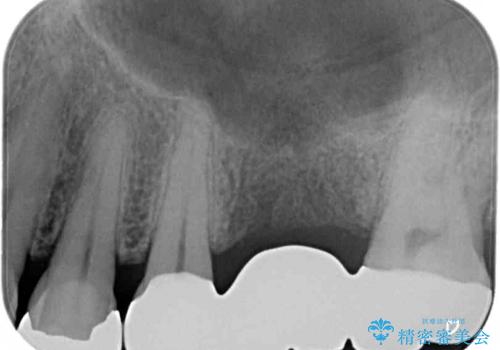

下顎の根管治療がされた大臼歯は咬合時に痛みが認められたため、再度根管治療を行った後に補綴治療することとしました。

むし歯は放置して改善することはあり得ませんので、早めの処置が大切です。